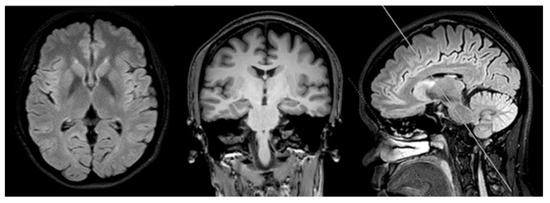

A 41-year old female college lecturer complained about slowness of thoughts and forgetfulness, which appeared a year before her first visit to the hospital. Unremarkable neurological findings were seen upon examination of the patient, and her MMSE and MOCA scores were 29/30 and 25/30, respectively. Addenbrook IIIR score was 93/100. She performed poorly on Wechsler’s logical memory test (score less than 1.5SD of norms). Her visual memory, language, attention, and executive functions remained normal. One year after the first symptoms, she resigned from her university position and started working in her family business. The patient’s mother was pleased that the patient had quit from her job, since she seemed to be anxious and often forgot her teaching schedule. She was diagnosed with pure amnestic-mild cognitive impairment (MCI) after one year from her first symptoms. MRI scans revealed mild cortical atrophy, especially in the precuneus region. No white matter lesion, lacuna infarction, or cerebral microbleed were observed in the brain MRI (Figure 1). APOE genotype of patient was homozygous for E3 allele.

Figure 1.

Magnetic resonance imaging of the brain (1.5T Philips) of the patient. No white matter lesion or lacunar infraction No medial temporal atrophy was detected. Mild global cortical atrophy for her age was detected.